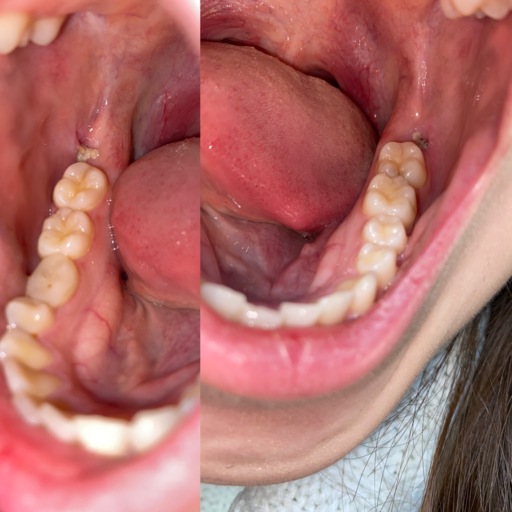

I have a very large cavity on one of my upper molars that caused severe pain for several weeks and went up through my sinuses. I live below the poverty level and have no insurance, but I headed to the ER because it was radiating out farther. I was put on penicillin and referred to our local, county health department where the only adult dental care offered is extraction. They have no anesthesia but did have Novocaine. He did an x-ray and said the roots were very deep but I know I don't have the option for a filling or root canal so I said that was fine. The Novocaine deadened every area of my mouth except the one nerve right in my tooth. I told him several times I was feeling pain, not pressure. After an hour of him attempting to extract the tooth, I had to have him stop because my whole body was shaking and I was sobbing no matter how much I tried to stop. I asked what now and there were no suggestions but he did inform me the tooth was still very firmly in my mouth and would not fall out on its own. For several days afterward, I had quite a bit of pain at the site of the injections (he injected in multiple locations 3 separate times)and the pain I had gone in with, though the radiating pain had stopped after completion of the penicillin. This was a month ago. I brush regularly and only use one side of my mouth to eat with because contact between the upper and lower teeth is very painful on the right side. This week, I have had some more aching but I figured I was just grinding my teeth again (yes, I have apnea and a bi-pap) but yesterday, the pain in the gum surrounding the tooth and roof of my mouth in the area where the dentist had done the injections returned as if he had been yanking on my tooth again. He did damage the tooth quite a bit during the attempted extraction with the ...pliers (not sure of the correct term) because I don't think he thought the tooth would be remaining. I am at a loss what to do now because I am already eating soft foods and the pain is bad enough, it woke me from sleep. I am taking an OTC NSAID, rinsing with salt water, and avoiding sugary or acidic foods. What else can I do?

Unfortunately, the pain will continue to return until the tooth is completely removed. The antibiotics will only temporarily calm the tooth but will not completely clear up the infection. The tooth needs to be removed as soon as possible. Since you have taken a round of antibiotics, the anesthetic may be more effective making the procedure more tolerable for you. Even though the tooth is not mobile, the decay will continue to get worse. Your body is constantly trying to fight the infection in your blood stream, weakening your entire immune system. It is very dangerous to have an untreated infection in your mouth, which is very close to your brain. Return to the dentist as soon as possible to have the tooth removed or find an oral surgeon that is able to remove the tooth. Waiting is only going to make the extraction more complicated as the tooth will continue to weaken and break down.